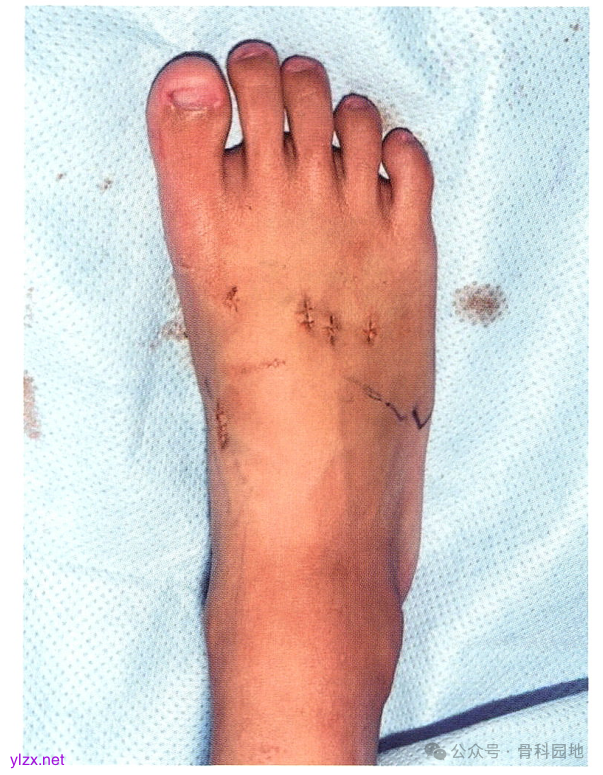

由于4 mm 骨皮质螺钉比 3.5 mm 螺钉或空心钉更坚固且更不易折断,所以建议使用4mm 骨皮质螺钉。但 3.5 mm 螺钉或空心钉对于小体格患者可能是足够的。如果使用空心钉,可以穿过克氏针拧人空心钉;但如果使用实心螺钉,只能从之前固定的克氏针旁边拧人。完成螺钉固定TMT关节,并用C臂机透视确认位置合适后,去除克氏针。

如果此时第 4/ 第 5TMT 关节仍然存在不稳定,需要复位后使用克氏针固定